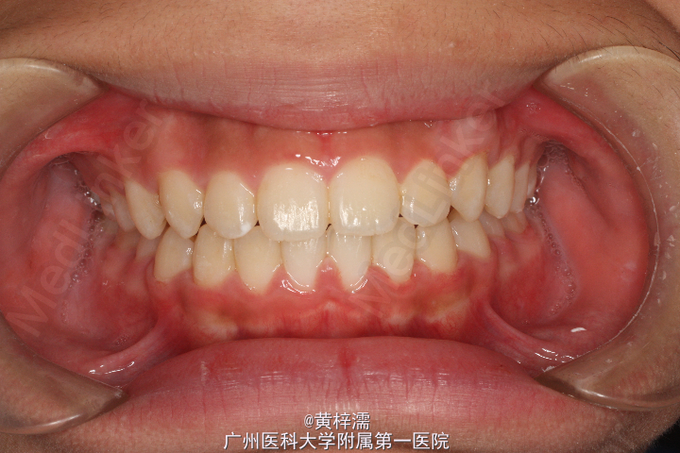

面部基本对称,无露龈笑,笑容不自然。直面型,面中1/3高度与面下1/3高度基本相等。下颌后缩,颏部发育稍不足。上中线与面中线一致,下中线稍右偏0.3mm。左侧磨牙关系中性,无尖牙关系。22,24间前庭沟下方可见鼓起,扪及23,磨牙覆盖正常。右侧磨牙关系中性,尖牙关系1/4远中,磨牙覆盖正常。上牙弓卵圆形,23缺牙间隙8.5mm,13宽度为8.5mm。口腔卫生可,未见牙体、牙周疾病,颞下颌关节检查未见异常。

诊断:安氏ǀ类错牙合;23埋伏阻生牙 处理:选择非拔牙矫治+23外科-正畸导萌术。全口固定正畸治疗,排齐阶段使用双丝技术牵引23,精细调整咬合关系及保持,总疗程18个月。

患者对治疗效果满意,拆除保持器维持1年。讨论:在判断阻生尖牙是否能自行萌出首先需判断阻生牙的倾斜角度及与侧切牙重叠位置,一般阻生超过侧切牙牙根1/2的阻生牙较难自行萌出,第二需要观察尖牙牙根发育状况而定。本患者尖牙已无自行萌出的趋势,因此行正畸牵引。 处理此类阻生尖牙时,首先粘接牵引附件需要确定牵引方向,控制牵引过程牙根不能碰及邻牙;其次牵引阻生牙时,牙列主弓丝必须时硬丝,利用短NITI丝段对阻生牙进行牵引,这样可以避免牵引过程对邻牙产生影响,稳定牙弓。第三,牵引后需要观察牙根方向和轴向,如不佳需要调整为好。